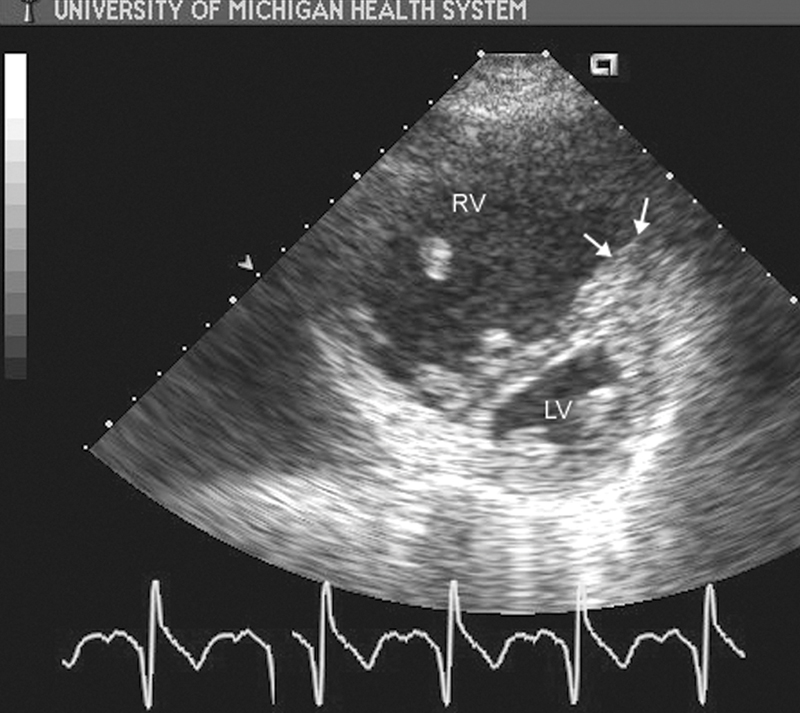

فحوصات تشخيصية لبعض امراض القلب والشرايين التاجية